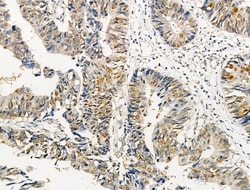

| Immunohistochemistry (Paraffin), Western Blot, Immunocytochemistry | |

| A synthesized peptide derived from human AKT1(Accession P31749), corresponding to amino acid residues around phosphorylated Ser124. | |

| Human, Mouse, Rat | |